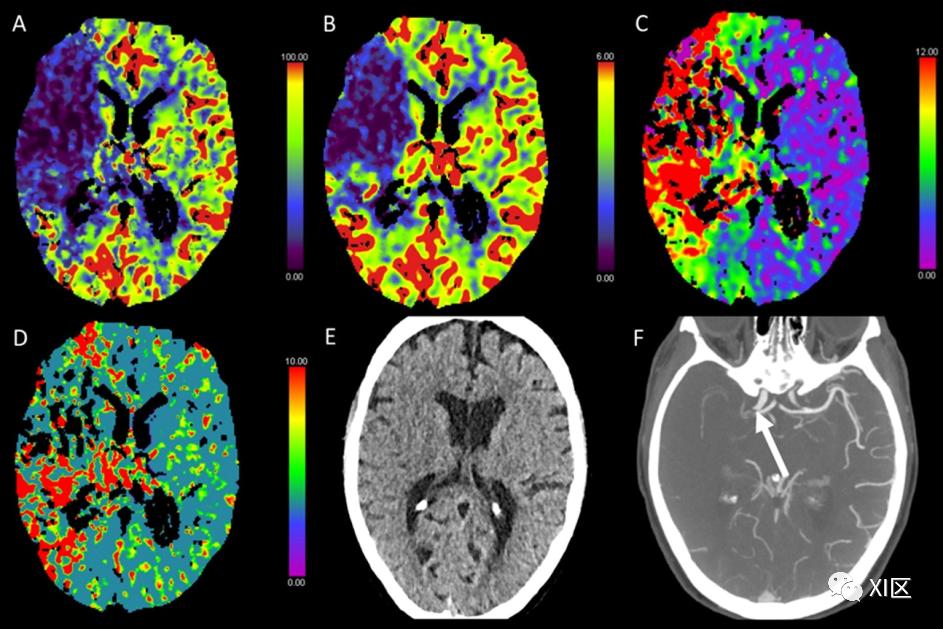

图1、图2、图3和图4给出了急性幕上卒中的例子。图5是一个恶性右侧MCA梗死的随访检查。

图1 脑部CTP产生的彩色编码图:(A)脑血流量量(CBF)[mL/100 g/min],(B)脑血容量(CBV)[mL/100 g],(C)Tmax [s],以及(D)平均通过时间(MTT)[s]。(E)CT平扫(NECT)和(F)动脉CT血管成像(CTA)。该患者接受了心导管检查,以关闭房间隔缺损。之后,该患者出现了左侧偏瘫。NECT显示灰白质分化略有减少。在右侧的大脑中动脉(MCA)区域,CBF和CBV降低,Tmax和MTT延长。CTA显示右侧颈内动脉远端闭塞。